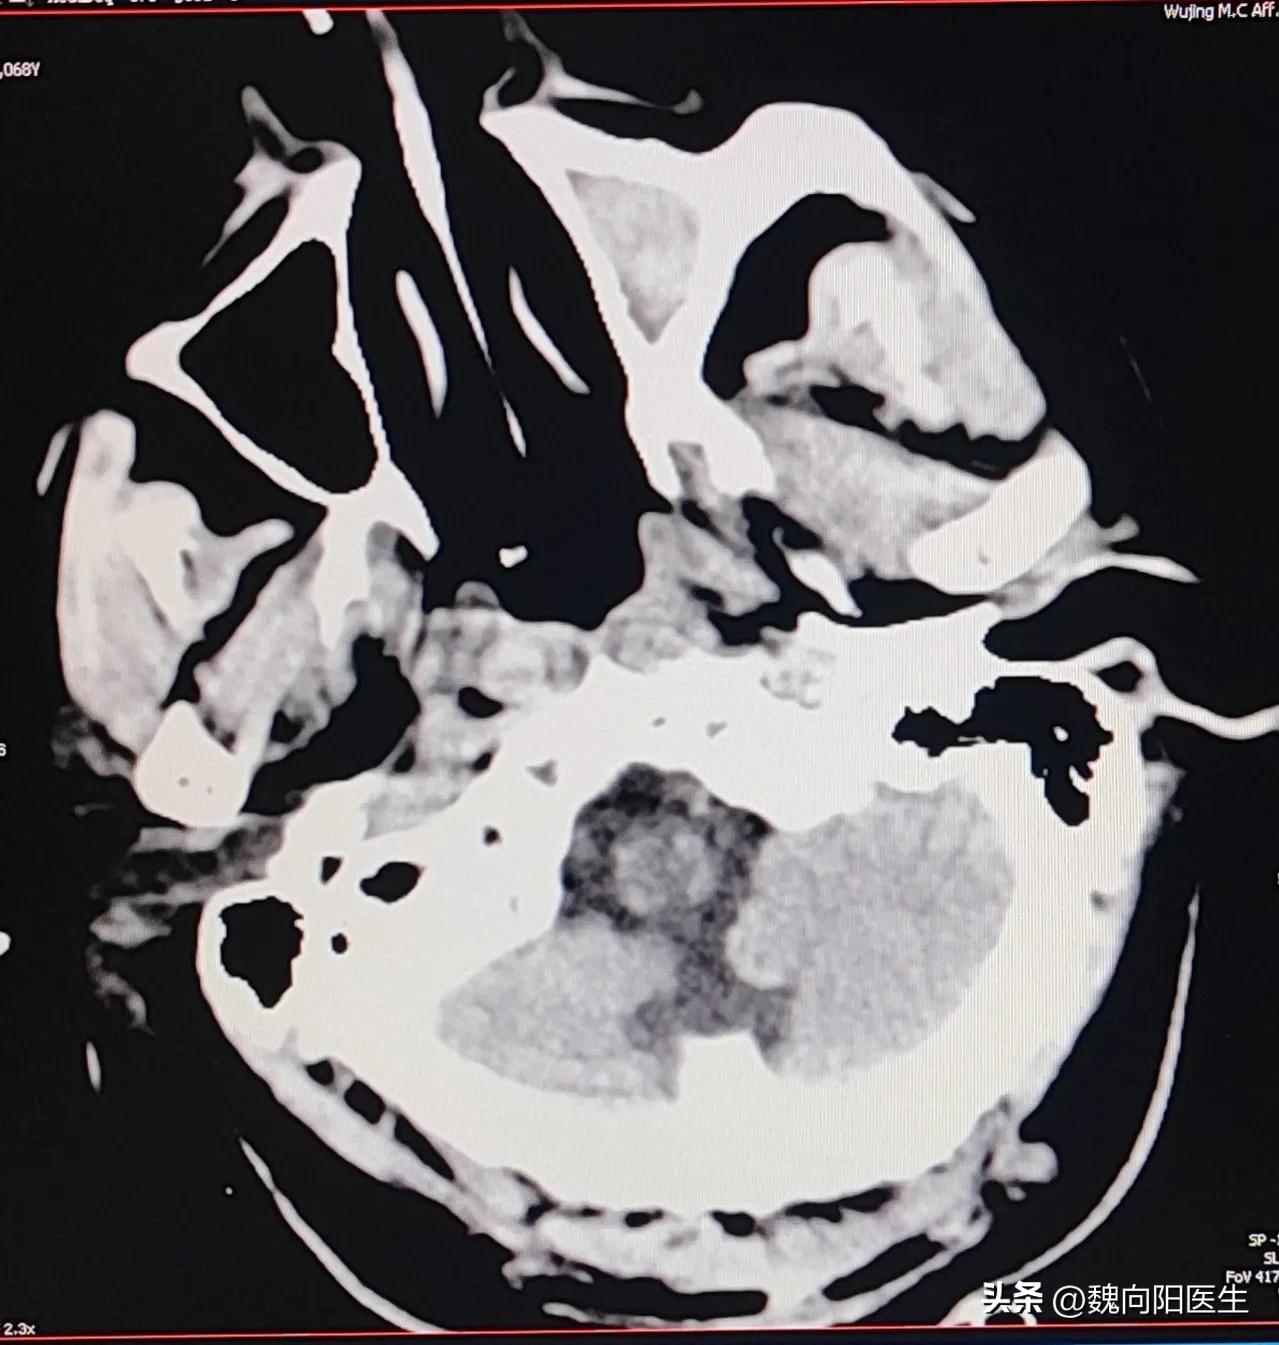

到中午之后复查头胸CT,确认是脑干梗死,同时合并吸入性肺炎。用上了广谱抗生素,下胃管,持续的抑酸治疗。

此时根据头CT的检查,考虑父亲存在闭锁的可能,一个清醒的人,脖子以下全不能动,甚至不能说话,只能用眼神来交流,那对他来说是多么的残忍,感觉老天太不公平了。